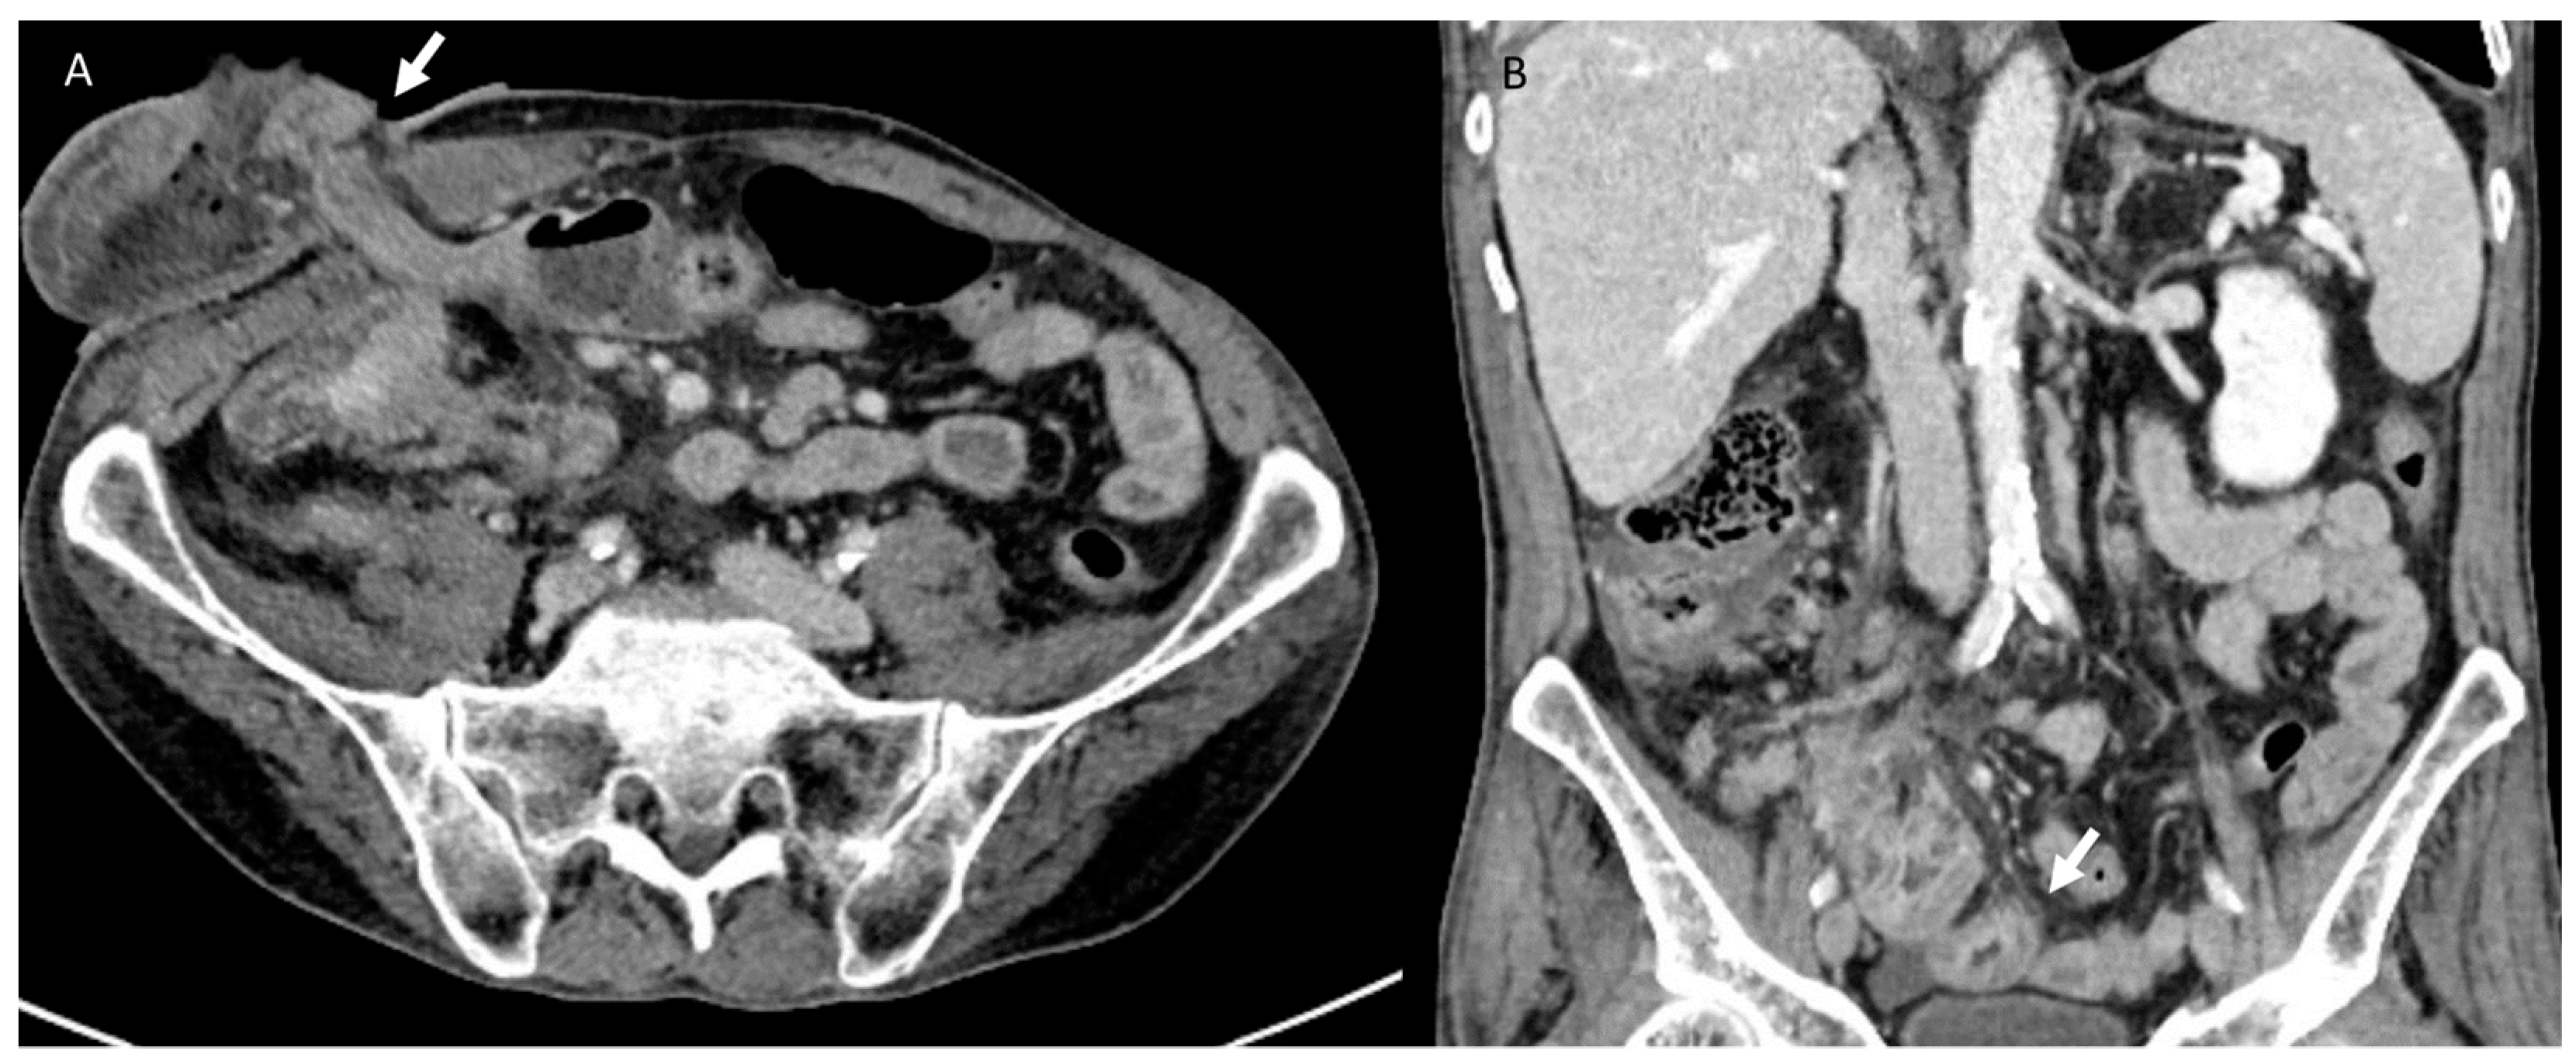

3.3. Bleeding

- Casal Núñez, J.E.; Vigorita, V.; Ruano Poblador, A.; Gay Fernández, A.M.; Toscano Novella, M.Á.; Cáceres Alvarado, N.; Pérez Dominguez, L. Presacral venous bleeding during mobilization in rectal cancer. World J. Gastroenterol. 2017, 23, 1712–1719. [Google Scholar] [CrossRef]